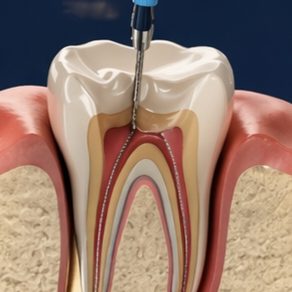

Painless, single-visit treatments using advanced rotary endodontics to save infected teeth.